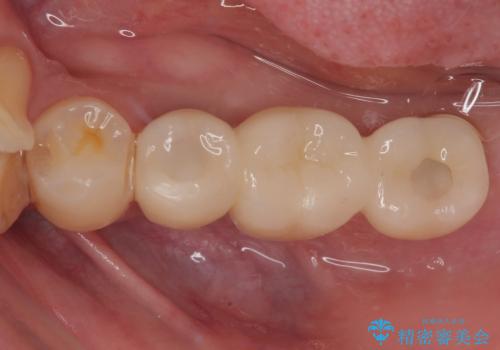

インプラント埋入時に十分な安定値を得ることができたため、速やかに仮歯を装着し、最小限の通院回数で治療を終えることができました。